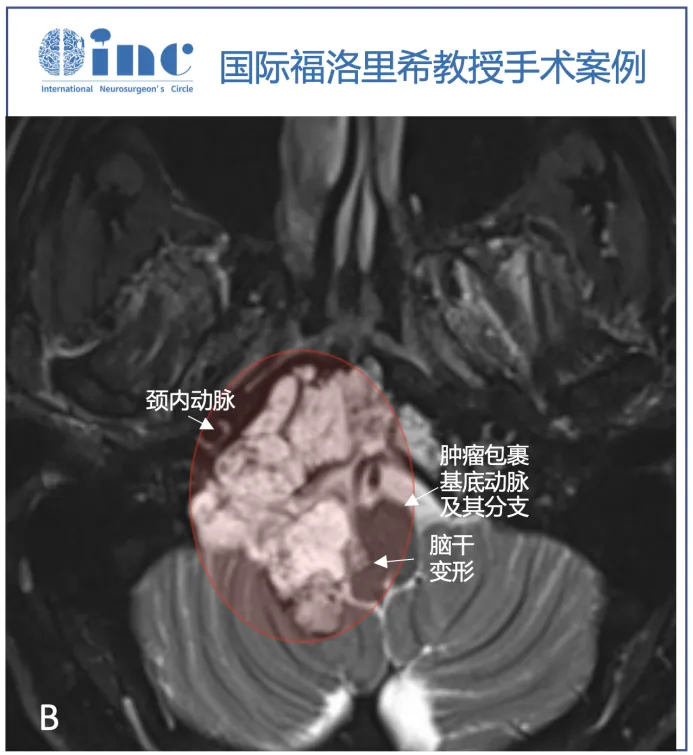

脑MRI检查显示颅颈交界处巨大轴外病变,提示脊索瘤,T1WI等强度,T2高强度,不均匀增强,以右侧岩斜坡软骨联合为中心,向下延伸至颅颈交界处,硬膜内延伸至Luschka孔,压迫脑干。肿瘤压迫小脑的最后部分也有增强,提示该部分肿瘤的颅底浸润和颅底血管化。右侧枕髁被肿瘤浸润并完全占据。由于肿瘤向外侧、硬膜内浸润生长,血管包膜和颅底浸润,内镜下鼻内入路被认为风险较高,实现完全切除的机会有限。

▼T2序列(B、C)上的多小叶形态和病变的生长模式,考虑脊索瘤。右侧枕髁被肿瘤完全破坏(C)。